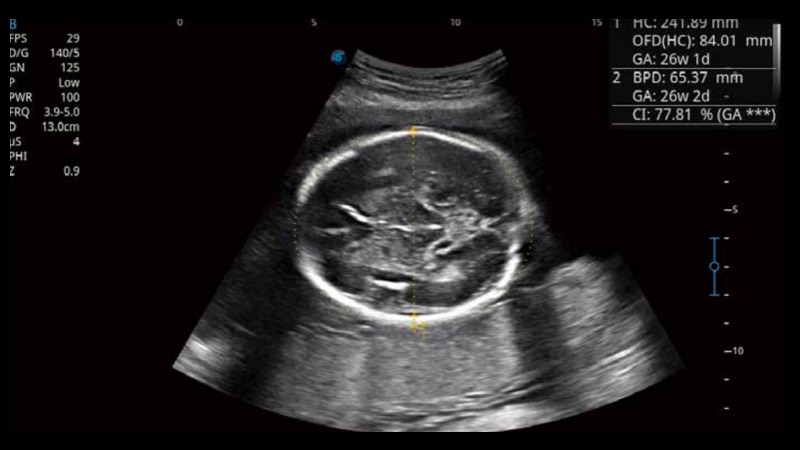

• 产科扫查助手S-Fetus

S-Fetus基于大数据深度学习算法,能够帮助您在产前筛查过程中智能识别胎儿标准切面、自动测量并录入报告。一个按键,即可智能、精准、高效地获取胎儿生理指标,极大简化您的产科检查操作。

• 产科自动测量Auto OB

可快速对产科扫查切面完成胎儿生理学参数的自动测量,减少操作者按键次数,大幅提升检查效率。